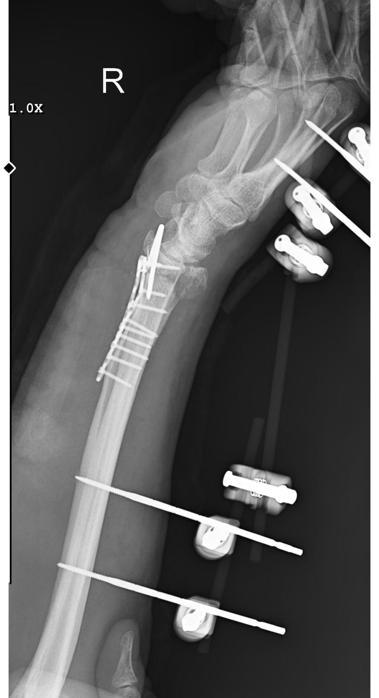

Olay, 29 Aralık tarihinde Yeşilbayır Mahallesi’nde gerçekleşti. Yasin Arslantaş, sabah işe gitmek üzere evinden çıktığında, aniden 9 sokak köpeğinin saldırısına uğradı. Köpeklerin üzerine doğru geldiğini gören Arslantaş, kaçmaya başladı. Ancak köpekler peşinden koşarak bacaklarından ısırmaya çalıştı. Arslantaş, bu durumu atlatıp yol kenarında park halindeki bir kamyonetin kasasına çıkmaya çalıştı. Fakat dengesini kaybedip düştü ve bu sırada yaralandı. Yardım istemek için 112 Acil Servis’i arayan Arslantaş, ambulansla hastaneye kaldırıldı. Sağ kolunda bilek kısmında parçalı kırık oluşan Arslantaş, ameliyat edilip tedavi sürecinin ardından taburcu edildi. Olay anı güvenlik kamerasına yansıdı.

Kolu askıda olan ve kontrolleri devam eden Arslantaş, “Sabah işe gitmek için evden çıktığımda arkamdan 9 köpek geldi. Bu köpekler oldukça saldırgandı. Aracın yanı başında bir pikap vardı. Köpekler peşimden saldırgan bir şekilde koştu. Kaydım ve düştüm. Doktorlar, bilekteki parçalı kırık nedeniyle tam iyileşmenin zor olduğunu ifade etti. Ayrıca his ve hareket kaybı yaşama ihtimalim olduğunu belirttiler. Ameliyat 3-3,5 saat sürdü ve 2 ay kadar fizik tedavi görmem gerektiği söylendi” şeklinde konuştu.